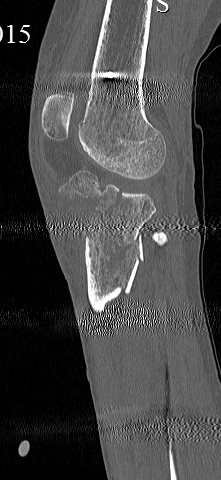

Серия КТ сканов в аппарате